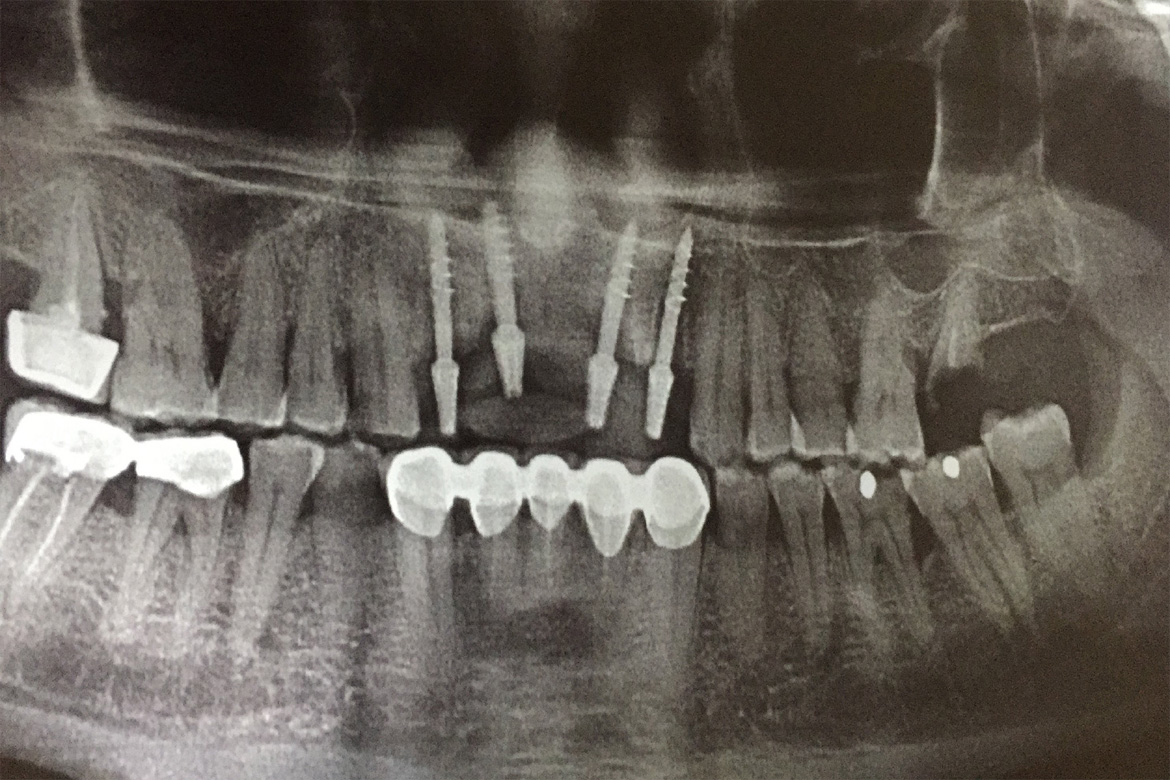

A Dental implant is a titanium post that is placed in your jaw bone which interfaces,integrates or interlocks (as in BASAL IMPLANTS) to provide a strong and secure foundation that replaces your missing teeth permanently.

They preserve the natural bone and also help stimulate fresh bone growth.

Though they are overpriced compared to other forms of restoration like the dentures and bridges its assets outweigh the expenditure in the long run.